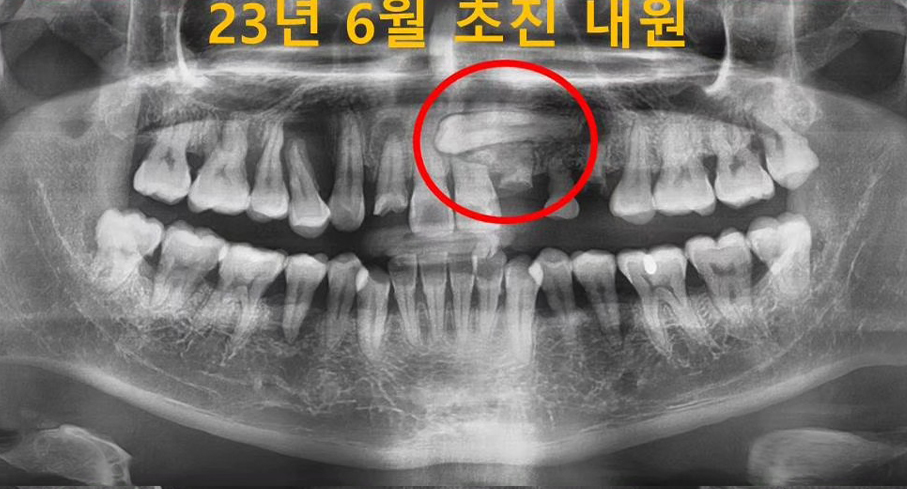

첫 방문에서는 정밀한 구강 검진과 함께 첨단 저선량 3D CT 촬영을 통해 여러분의 구강 상태를 정확히 파악합니다. 전신 건강 평가도 함께 이루어져 체계적인 치료 계획의 토대를 마련합니다.